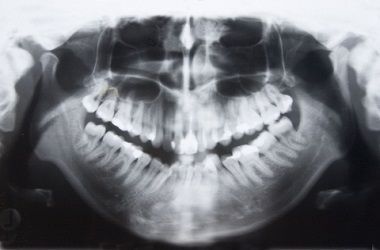

Spesso una normale "panoramica" non è sufficiente in quanto all'immagine manca la profondità. È molto più indicata una Tac che, tramite un apposito software chiamato Dentalscan, permette di valutare lo spessore dell'osso, la sua trama e la distanza da rispettare rispetto alle strutture vitali. La possibilità di inserire degli impianti è strettamente legata alla quantità di osso residuo che va valutata per ogni singolo paziente.

Non sempre ogni dente necessita di un proprio impianto, ad esempio nella figura accanto possiamo vedere quattro denti sostenuti da tre soli impianti.